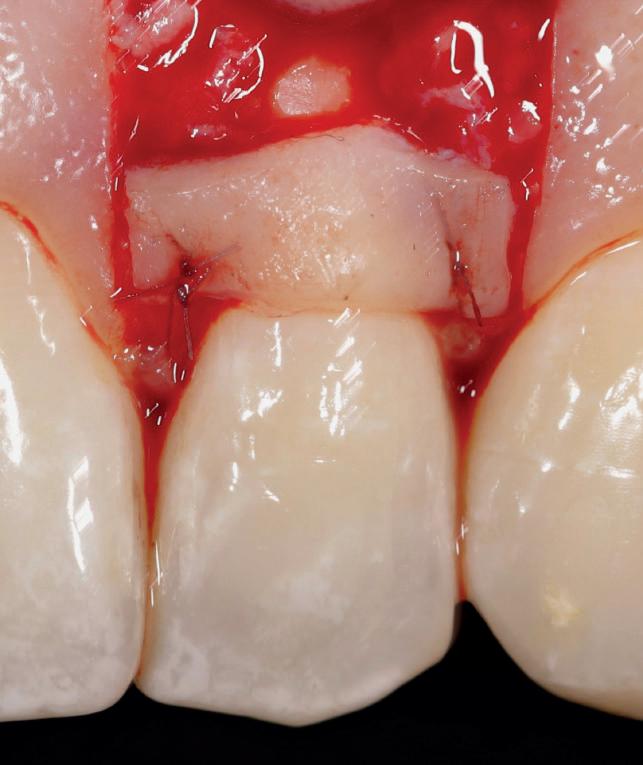

CASE STUDY

Guided implant approach for reproducible results, page 28

1. Adaptable to different guided surgery protocols: piloted, semi-guided or fully guided.

2. No friction between drills and guide sleeve, no overheating and no release of particles.

3. No specific drills and a very small surgical box.

4. Full control of drilling depth.

5. Your conventional driver-guided drilling sequence.